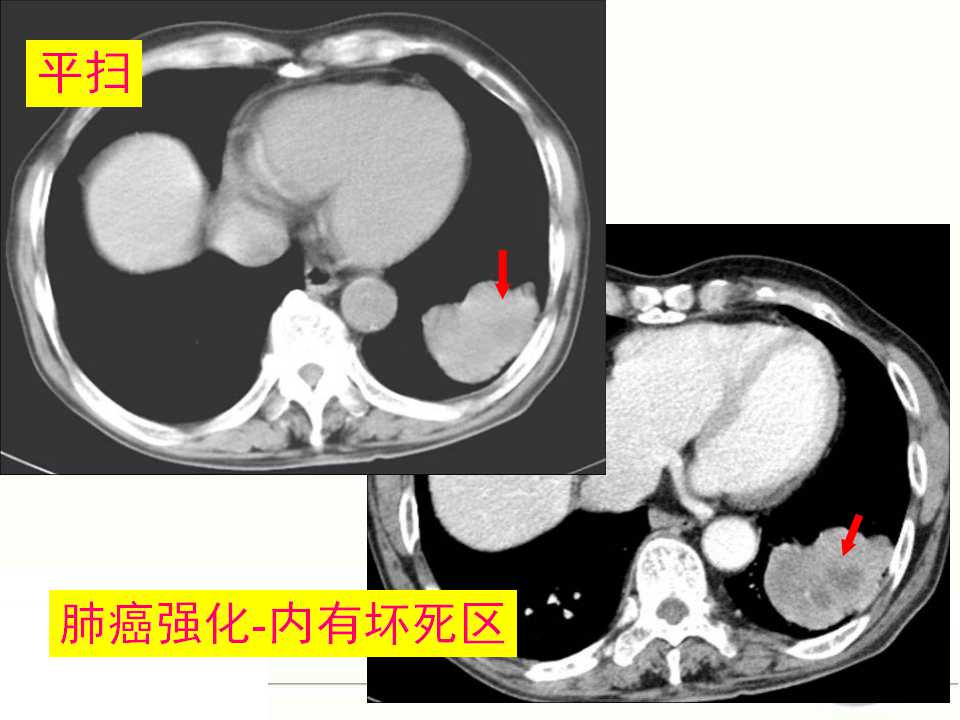

肺癌的影像学检查